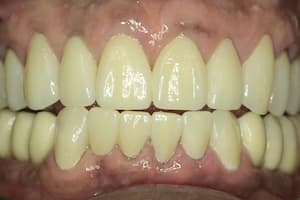

До

После

Удаление 7 зубов, установка 11 имплантов Straumann, временное и постоянное протезирование всех зубов с учетом формы, цвета и размера зубов. Работа с мягкими тканями. Импланты использовались для немедленной нагрузки.